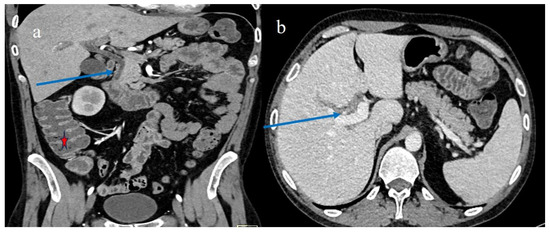

| 1 | P | P | Multisegmental and plurifocal parietal thickness with homogeneous mucosal enhancement on distal ileus | Multisegmental thickness with homogeneous mucosal enhancement | Mild diffuse comb sign and poor reactive mesenteric lymph node | Splenic infarct |

| 2 | P | P | Diffuse parietal thickness with stratified enhancement | Multisegmental thickness with homogeneous mucosal enhancement | Diffuse comb sign and poor reactive mesenteric lymph node | Mild gallbladder thickness and mild biliary tract dilatation |

| 3 | P | P | Multisegmental thickness with stratified enhancement at the terminal ileus (on CECT control at 92 days). The CECT control at 129 days showed persistence of mild parietal thickness at terminal ileus and with mucosal enhancement | Diffuse parietal thickness with stratified enhancement (On CECT control at 92 days) The CECT control at 129 days showed colic fluid distension with mild diffuse mucosal enhancement | Diffuse comb sign, mild ascites, and poor reactive mesenteric lymph node | Hepatomegaly and mild gallbladder thickness |

| 4 | P | P | Intestinal diffuse homogeneous thickness with homogeneous mucosal enhancement (on CECT control at 66 days after the HSCT); diffuse small bowel involvement with increased parietal thickness on CECT control at 120 days | Appearance of multisegmental thickness on sigma and descending colon and stratified enhancement on transverse colon on the CT FU at 120 days | Diffuse comb sign and poor reactive mesenteric lymph node | Mild gallbladder thickness and persistence of biliary tract dilatation on follow-up CT |

| 5 | P | P | Multisegmental thickness with stenosis on jejunal loops and SBO and segmental and focal thickness on the terminal ileus and appendix | Diffuse parietal thickness with stratified enhancement | Mild comb sign, poor reactive mesenteric lymph node, small air bubbles in the ascites | Small splenic areas of ischemia |